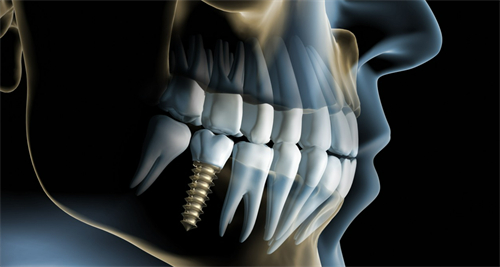

韩国登腾种植牙:5980元起/颗

韩国奥齿泰种植牙:7000元起/颗

美国百康种植牙:7500元起/颗

美国3i种植牙:7800元起/颗

德国费亚丹种植牙:8250元起/颗

德国icx种植牙:8800元起/颗

意大利BB种植牙:9500元起/颗

法国安多健种植牙:10000元起/颗

瑞典Astra种植牙:15800元起/颗

瑞士ITI种植牙:11500元起/颗

瑞典诺贝尔种植牙:12000元起/颗

纯钛基台种植牙:6299元起/颗

两段式种植牙:7399元起/颗

德国卡瓦ATID超短种植牙:5599元起/颗

钛锆种植牙:5399元起/颗

半口种植牙:44940元起

全口种植牙:98405元起

全口固定式种植牙:125868元起

全口插接式种植牙:128951元起